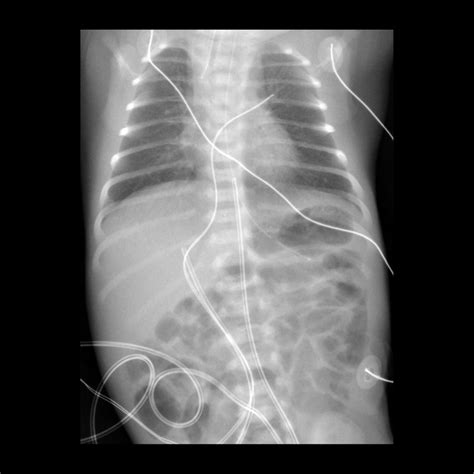

3. Insertion: The catheter is gently inserted into the umbilical vein, which is identified by its larger size and bluish color compared to the arteries. The catheter is advanced until it reaches the desired position, typically confirmed by ultrasound or X-ray.

5. Verification: The position of the catheter is verified using imaging techniques to ensure it is correctly placed in the inferior vena cava.

• umbilical venous catheter x ray